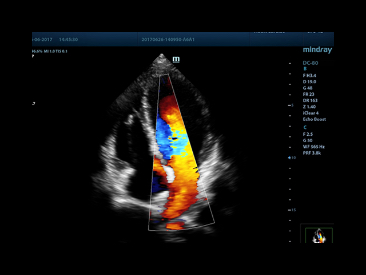

Cardiac_2D

Four chamber View